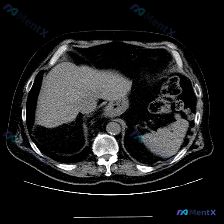

看到一个很有意思的读片请求,预设是“脾脏病变”,但拿到的影像和分析报告却很值得拿出来讨论思路。 先把客观资料整理清楚: 基础影像信息 - 检查方式:单张上腹部CT横断面(软组织窗) - 影像描述: - 脾脏:形态正常,实质密度均匀,未见梗死、囊肿或占位性病变 - 肝脏:实质密度尚均匀,未见明显占位,...

今天看到一份很有意思的影像资料,提问直接指向“脾脏特异性异常”,但仔细读完图像和分析,发现里面藏着一个很典型的临床思维陷阱,整理一下思路和大家分享。 先看这张CT的客观发现 这是一张腹部CT横断面软组织窗图像: 1. 脾脏:形态可见,密度均匀,没有看到明确的增大,也没有局灶性的高低密度病变; 2....